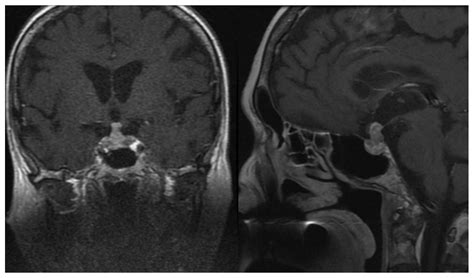

• Imaging studies: Magnetic resonance imaging (MRI) is the gold standard for visualizing the pituitary gland and the infundibular stalk. It can detect tumors, inflammation, and other structural abnormalities.